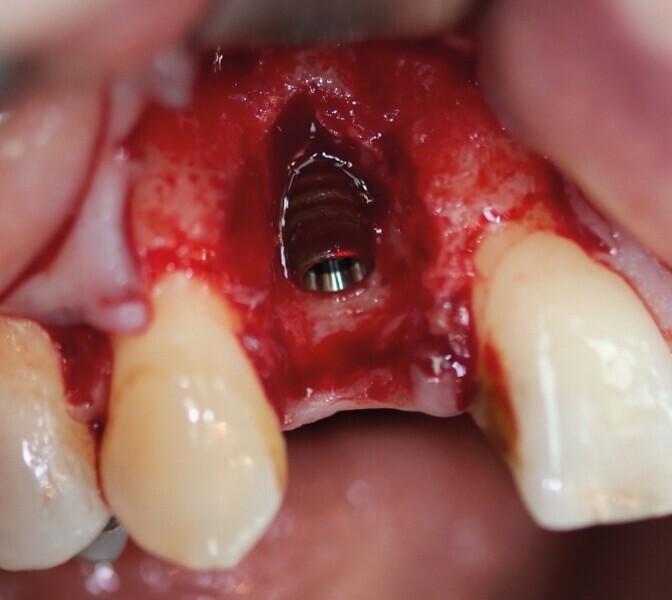

Dans les cas cliniques présentés dans cet article, la carotte osseuse fournit une table osseuse de forme circulaire, et son immobilisation est par impactage et non par vissage. Ce sont ces deux particularités qui nous permettront de placer l’implant dans le même temps opératoire. En effet, la carotte osseuse est désépaissie en la coupant en deux en épaisseur. Une partie est transformée en copeaux d’os et mélangée à l’os de forage, récupéré dans les rainures des forets BLT Straumann (Fig. 15). Une fois l’implant parfaitement ancré (Fig. 16), cet os particulaire est placé contre la surface implantaire (Fig. 17). La rondelle corticale restante est impactée et sert ainsi de mur vestibulaire (Fig. 18). Cet ensemble se retrouve parfaitement dans les contours osseux. L’implant ayant une stabilité primaire suffisante, une dent provisoire en composite sur pilier PMMA est transvissée.

Pour connaître la profondeur de trépanation, il suffit d’enfoncer la sonde parodontale et de mesurer l’épaisseur de gencive sur l’os. En y ajoutant 4 mm, la profondeur finale est obtenue pour avoir suffisamment d’os. Une fois la carotte ostéogingivale prélevée (Figs. 23 et 24), il ne faut pas séparer l’os de la gencive, mais réduire l’épaisseur gingivale en supprimant la partie kératinisée (Fig. 25). Un implant cylindroconique (Straumann BLT 3,3 SLActive Roxolid) est parfaitement ancré (Fig. 26). La carotte d’os et sa gencive toujours adhérente, sont alors impactées transversalement à l’implant (Fig. 27). La partie osseuse spongieuse est au contact de l’implant, pendant que le conjonctif qui y est attaché, est utilisé comme un greffon conjonctif enfoui sous le lambeau vestibulaire.